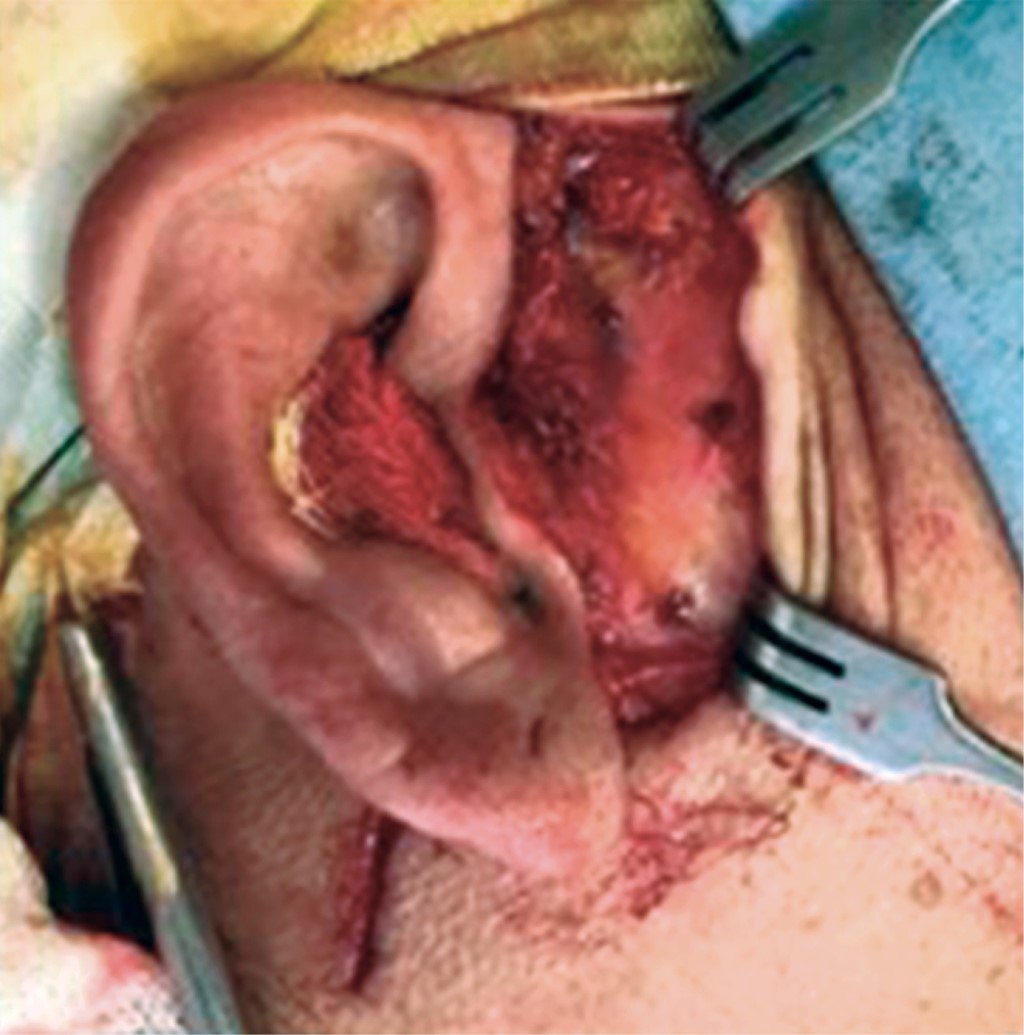

Se inicia la planeación quirúrgica y se decide realizar biopsia excisional de la lesión para confirmación diagnóstica mediante estudio histopatológico, bajo anestesia general balanceada con intubación orotraqueal, previa asepsia y antisepsia se delimita el campo quirúrgico, se protege el conducto auditivo externo con una gasa, con tracción digital de la región preauricular derecha se realiza marcaje de arriba hacia abajo comenzando en la circunferencia del hélix, extendiéndonos endauralmente por la superficie interna del trago hasta la unión con el lóbulo de la oreja7 (Figura 5), en este caso se realizó una extensión retroauricular. Se infiltra lidocaína con epinefrina de 2% en la región preauricular para mayor vasoconstricción. Realizamos incisión con hoja de bisturí número 15, se diseca por planos iniciando por piel, tejido celular subcutáneo, fascia temporal superficial, teniendo en cuenta que a este nivel encontramos las ramas del nervio facial, se continúa hasta llegar a la cápsula articular, en donde se observa la lesión bien delimitada en el compartimiento superior de la articulación (Figuras 6, 7 y 8). Se valora la adecuada función de la articulación, correcta migración del cóndilo en la cavidad glenoidea, se posiciona el disco articular y se realiza cierre de planos profundos, a nivel de piel se colocan puntos subdérmicos (Figura 9). Se obtiene la muestra completa de aproximadamente 4.5 × 2 × 1 cm (Figura 10), y se envía para estudio histopatológico el cual reporta: "en los cortes histológicos examinados se observa membrana sinovial con hiperplasia de la íntima y que en la subíntima presenta múltiples nódulos compuestos por cartílago hialino maduro. Algunas áreas son hipercelulares con atipia leve de los condrocitos. Entremezclado con áreas de osificación y otras de aspecto mixoide". Con diagnóstico de condromatosis sinovial.

Figura 6

Figura 7

Figura 8